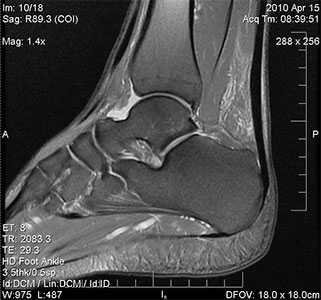

МРТ голеностопного сустава

МРТ для диагностики недуга не является обязательным исследованием. Его выполнение рекомендуется, если необходимо провести дифференциальную диагностику с другими патологиями либо в начальных стадиях патологии.

- МРТ плечевого сустава. Назначается для подробного изучения мягкотканных структур: вращательной манжеты, сухожилия двуглавой мышцы, суставной губы. Обнаруживает даже незначительные дефекты (надрывы) признаки дегенерации и воспалительного процесса.